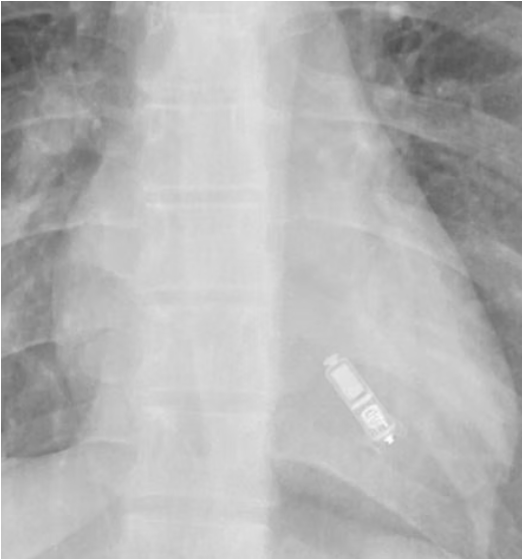

🫀✅ Answer: Micra leadless pacemaker⚡️ 📍Typically implanted in the right ventricle (via femoral venous access) 🔑 Imaging clue: small capsule-shaped device overlying the cardiac silhouette with small spider-like "fixation tines" Bonus pearl: if you see it somewhere that’s

🫀📷 Unknown device time… Spotted on CXR: a tiny metallic “capsule” overlying the heart 📷 👀What cardiac device is this? Bonus: where is it typically implanted? Drop your guess 👇 #Radiology #Cardiology #CXR #MedTwitter #Radres